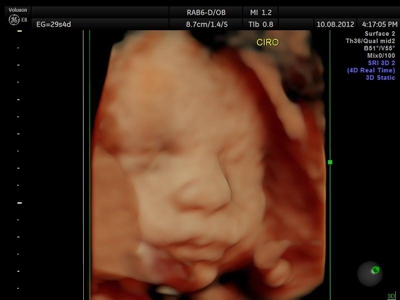

La ecografía 4D HD/5D consiste en la adquisición y presentación continúa de volúmenes. La denominación de la técnica obedece a que hay cuatro dimensiones involucradas: ancho, largo, profundidad y tiempo.

Si bien la Ecografía 4D HD/5D puede realizarse en cualquier etapa del embarazo, recomendamos realizarla entre las semanas 24 a 32 de gestación ya que se pueden observar rasgos bien definidos en el bebe.

Fotografías de ecografías 4D HD/5D

Haga click sobre las imágenes para ampliar